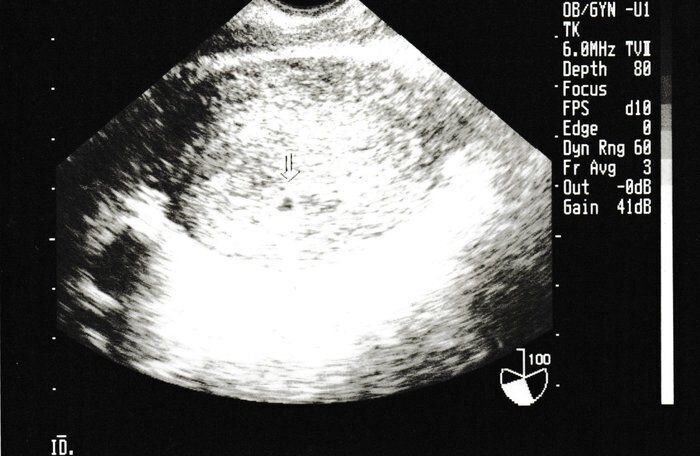

クリコさんの妊娠4週目のエコー写真

生まれて初めての内診。恥ずかしさと、痛みを心配をしている間に終了。胎嚢は確認できたけど、まだ心拍は確認できないので、来週また来てくださいとのこと。また、この時期は初期流産の可能性も高いという話をされて、一気に心が沈みました。確かに、普通なら妊娠に気づかないような超初期。でも、確実に命の始まりがあることがわかり、「流産はしたくない!」と思い続けて過ごしました。